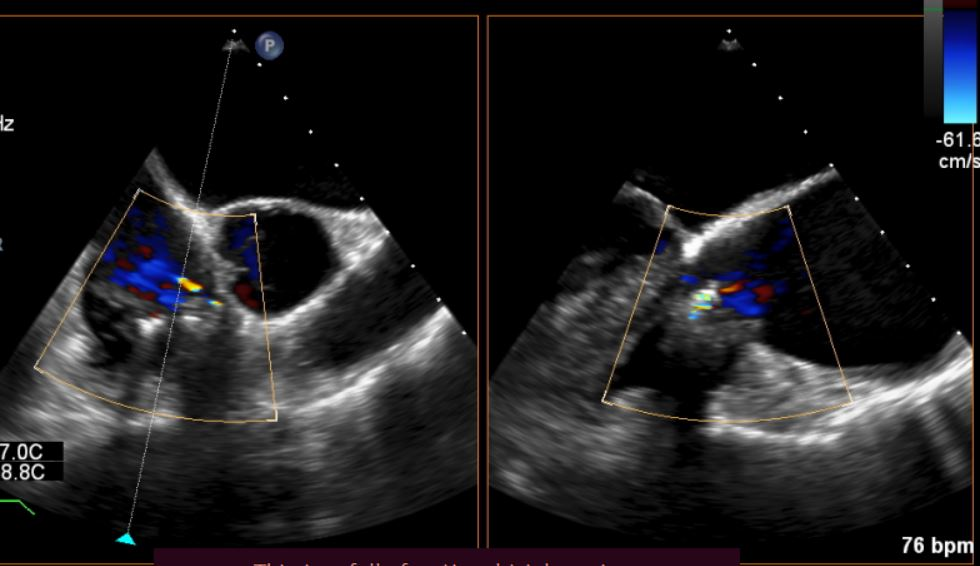

同时其夹子系统继承于申淇淇麟经导管二尖瓣缘修复系统的优秀设计,具备四个不同型号的夹子及瓣叶分开捕获能力,从而使用更加复杂多变的三尖瓣解剖。因该患者三尖瓣反流束较宽,瓣叶存在较宽的关闭裂隙,术中很好的利用了瓣叶分开捕获的功能,于前隔瓣区域行瓣膜缘对缘修复。夹子植入后,患者反流明显减轻至轻度(视频2/图3)。患者术后回复良好,出院前TTE提示轻度反流。

图片

图3:术后TEE提示三尖瓣反流明显减轻